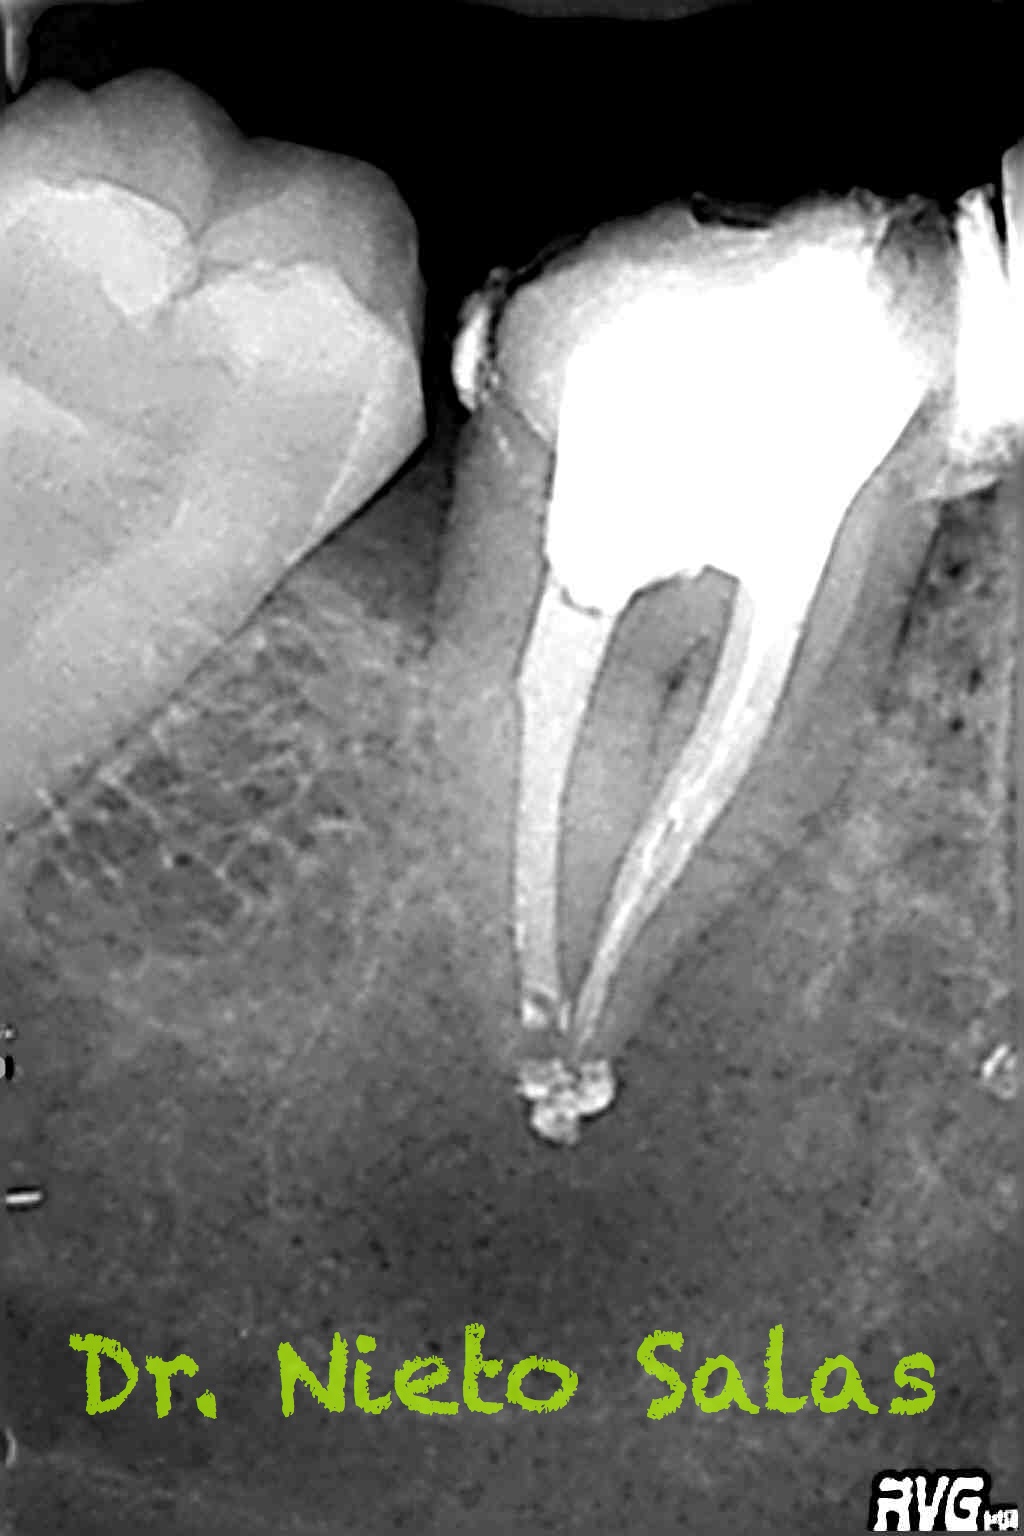

Nos remiten a la clínica a una paciente con un tratamiento previo de endodóncia realizado ya hace unos 5 años y que presenta una agudización del proceso. Se trata de un fracaso endodoncico por una falta de sellado tanto coronal como apical, en el que en el espacio intra-conductos nos encontramos dos léntulos, y en el acceso a los mismos un perno prefabricado.

Usamos técnica de obturación por ola continua de Buchanan modificada y hacemos un backfilling con gutapercha inyectada.

Con respecto al caso, bueno ya sabrás que trabajando con mágnificación, hay cosas que son más fáciles de lo que parecen, y con ultrasonidos, microdebraiders y paciencia todo salió bastante fácil.

Dentro de los ultrasonidos, removí el perno con una ET20 de Satelec y ProUltra nº4 y ET25 para los léntulos.

Presentaba un sistema de conductos en el que el conducto distal era acintado y los mesiales podían unirse después de instrumentarlos.

Me gusta ser conservador con los diámetros apicales, para deformarlos lo menos posible. En este caso no fue así por la anatomía que presentaba, adapté bien los conos maestros con un diámetro más o menos 45 en el conducto distal(recuerda que era acintado con lo que no es posible un único cono apical) y 30 los mesiales.